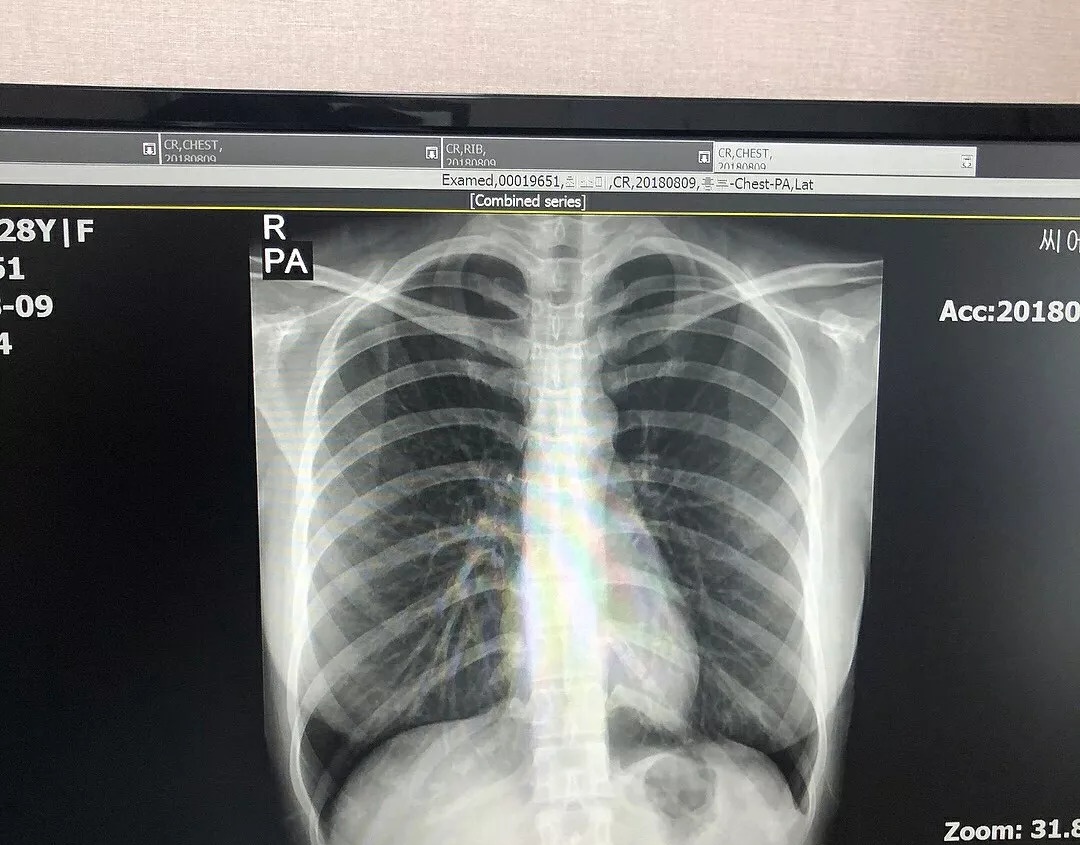

她在INS上上传了自己胸部的X光扫描图…力证自己胸部发育纯天然,并表示隆胸什么的不存在啊不存在。

崔素美小姐姐表示这些诊断内容是经过医生本人同意后,才被她po在网上的,希望通过这次的澄清可以平息网络上的传闻。